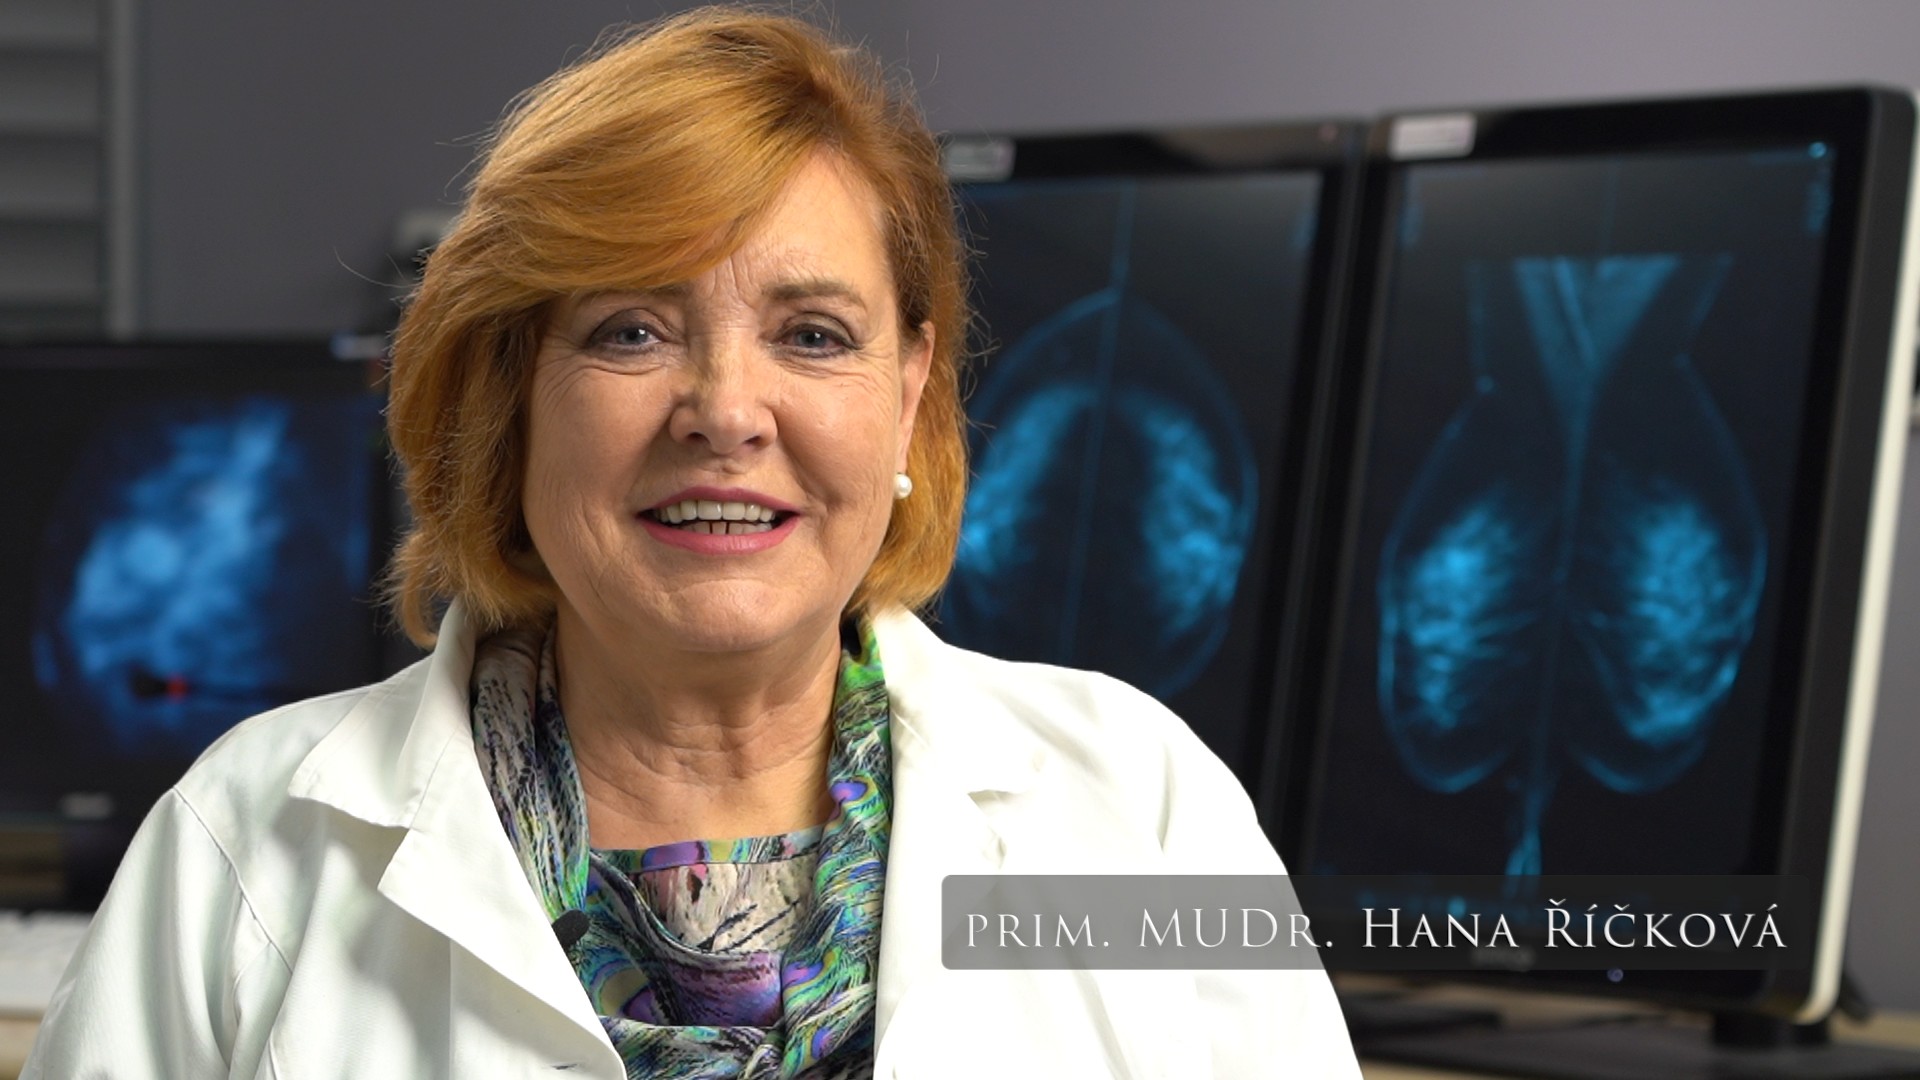

Ukázky našich realizací